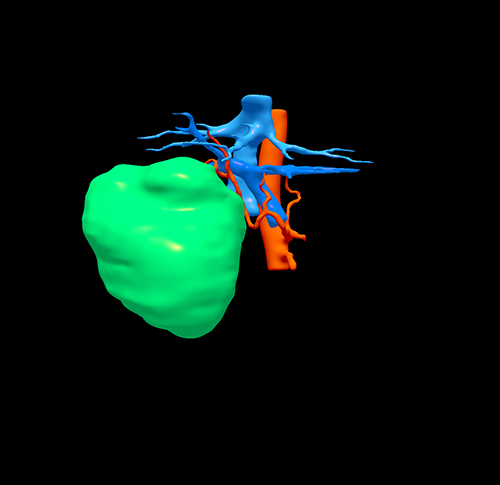

右肝巨大肝癌---右半肝切除